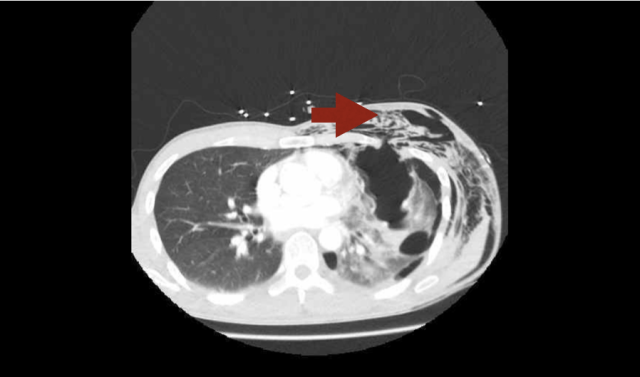

Pneumothorax is often associated with subcutaneous emphysema (free air in the tissues under the skin). It feels like bubble-wrap and looks like this on CT. Don’t press too hard though – it’s likely there are rib fractures underlying the air and they are extremely painful!